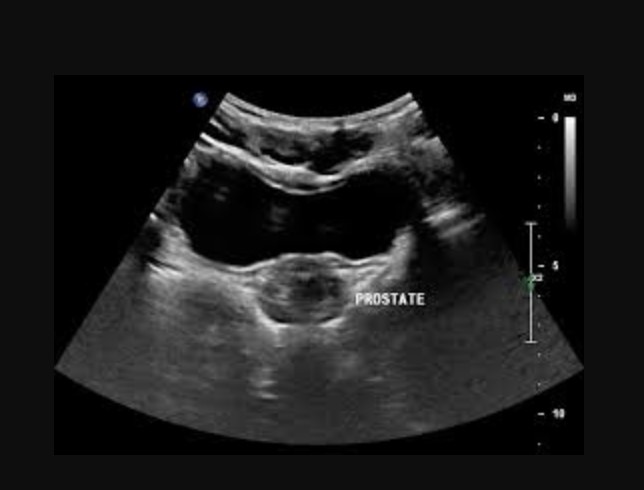

The prostate gland is a structure that surrounds the neck of the bladder and urethra with ducts that enter into the urethra. This diagnostic code involves conditions of the prostate gland including: any nonmalignant infection; trauma; benign prostatic hypertrophy (BPH); or a surgical procedure in which the reproductive or bladder function is impaired.

Tests done to investigate prostatic disorders may include, but are not limited to the following: urinalysis; intravenous urography; uroflowmetry; cystourethrography; and determination of the prostate-specific antigen (PSA) values. In addition, tests to evaluate creatinine levels, blood urea nitrogen (BUN), and phosphate and calcium levels may be done to determine if metastasis to the bone has occurred. Other diagnostic measures may include: prostatic biopsy; ultrasound; magnetic resonance imaging (MRI); and computed tomography (CT) scan.